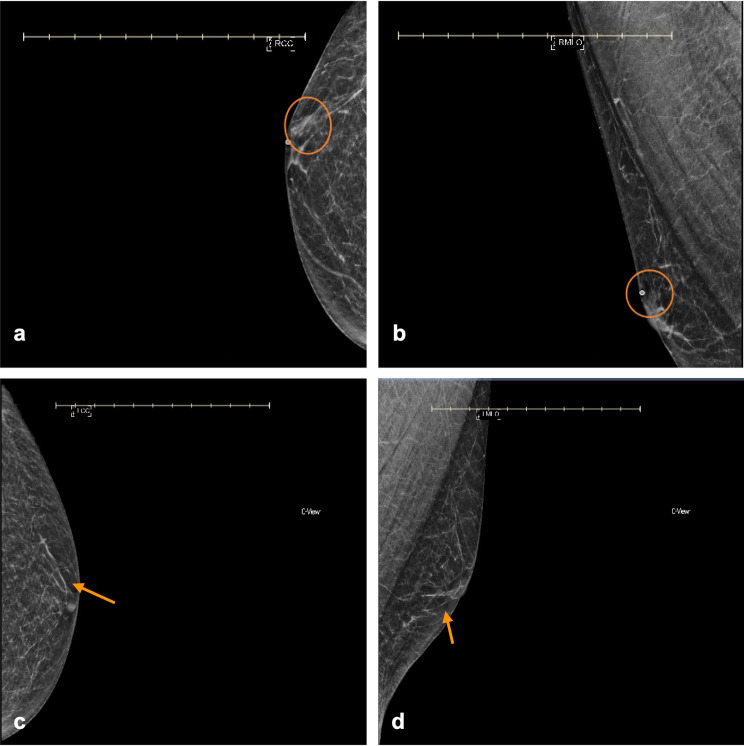

Case presentation: This report presents a unique case of PASH in a senior adult male, aged over 65 years, who presented with an enlarging palpable areolar mass. Notably, the patient had no family history or past medical history of breast cancer. Imaging studies, including mammography and ultrasound, revealed mild gynecomastia and BIRADS-4 classification, prompting further investigation. A core needle biopsy confirmed the diagnosis of PASH, showing no evidence of carcinoma or malignancy. Given the mass's progressive enlargement, surgical excision was recommended and successfully performed.